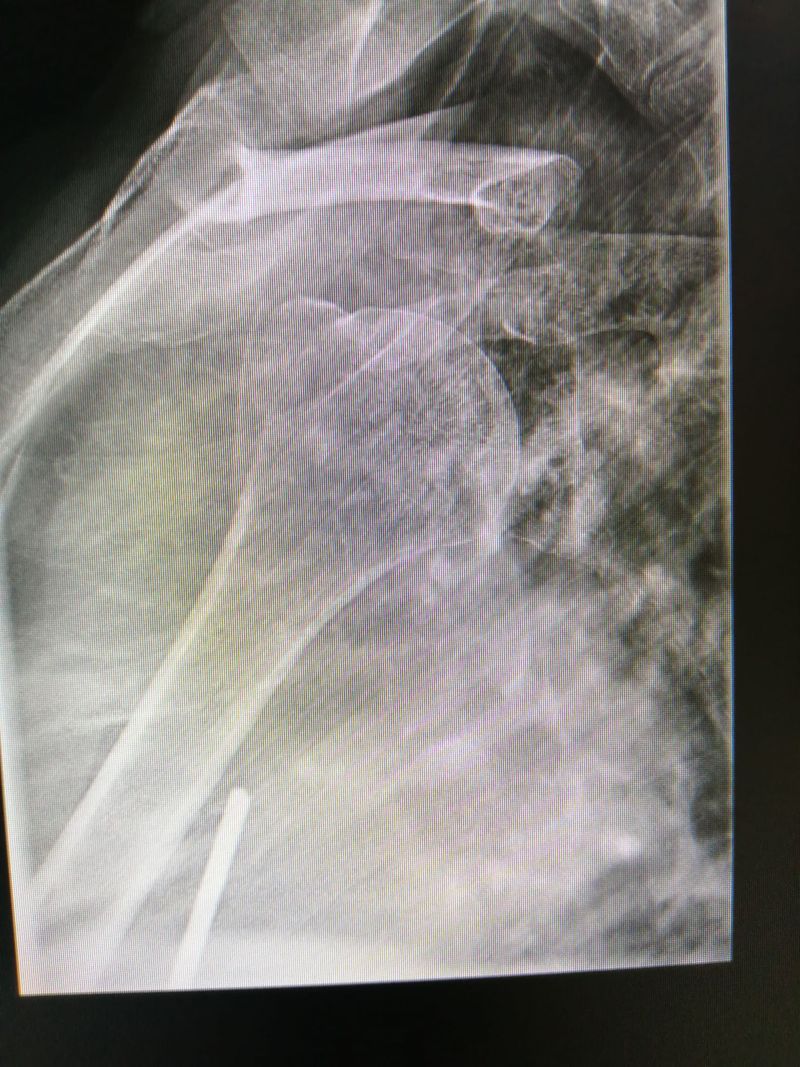

Transthoracal view

fracture of the greater tuberosity.

Xray

Fracture

Tuberculummajus